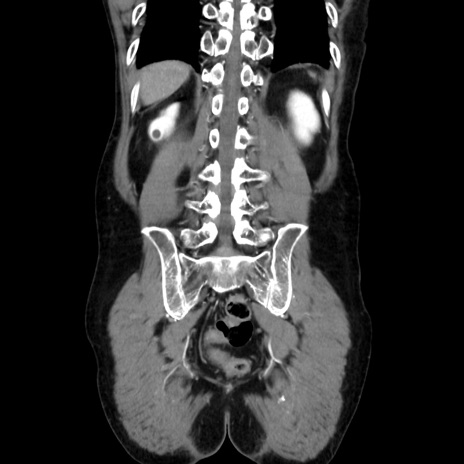

症例37(冠状断像)

【症例】40歳代 男性

【主訴】腹痛

【現病歴】4時間ほど前に電車に乗車中に臍部上より腹痛出現。徐々に増悪し起立困難となり、救急外来受診。生ものは数日食べていない。今朝お雑煮を食べた。

【身体所見】BT 36.8℃、BP 117/84mmHg、HR 91/min、SpO2 97%、苦悶様、腹部:臍上部広範囲圧痛あり、反跳痛±

【データ】WBC 8100、CRP 0.03